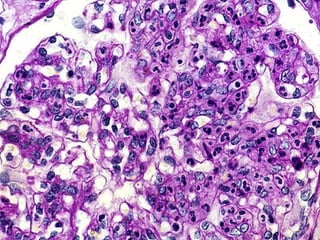

HistopatologíaHistopatología

LesionesLesiones glomerulares mínimas.glomerulares mínimas.

Fusión de podocitos.(inflamacionFusión de podocitos.(inflamacion ))

Proliferación mesangialProliferación mesangial moderada.moderada.

Inmunofluorescencia negativaInmunofluorescencia negativa

Alteraciones histológicasAlteraciones histológicas

ProliferaciónProliferación celularcelular

Infiltración leucocitariaInfiltración leucocitaria

Engrosamiento/alteración MBGEngrosamiento/alteración MBG

Hialinización o esclerosisHialinización o esclerosis